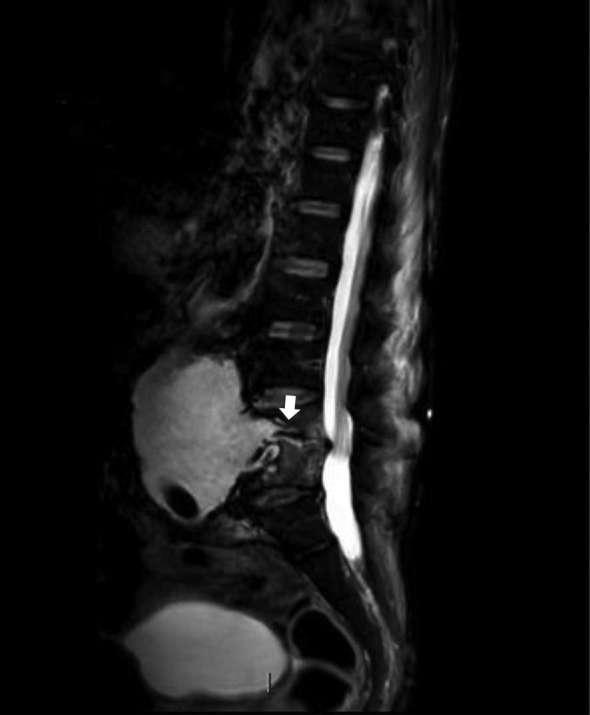

We present the case of a 68-year-old male, who underwent open abdominal aortic graft in August 2016 owing to a ruptured large infrarenal abdominal aneurysm. He subsequently presented 6 months later with back pain, general weakness, reduced mobility and cachexia. He underwent CT, MRI and fluorodeoxyglucose (PDG)-PET spinal imaging, all modalities showing signs of aortic graft infection complicated by L4/5 discitis. The patient was treated conservatively with intravenous antibiotics and spinal brace support, as his general condition did not allow for surgery. Although he showed initial clinical improvement allowing plans for supported discharge, his improvement was not sustained and he died 4 months after admission.